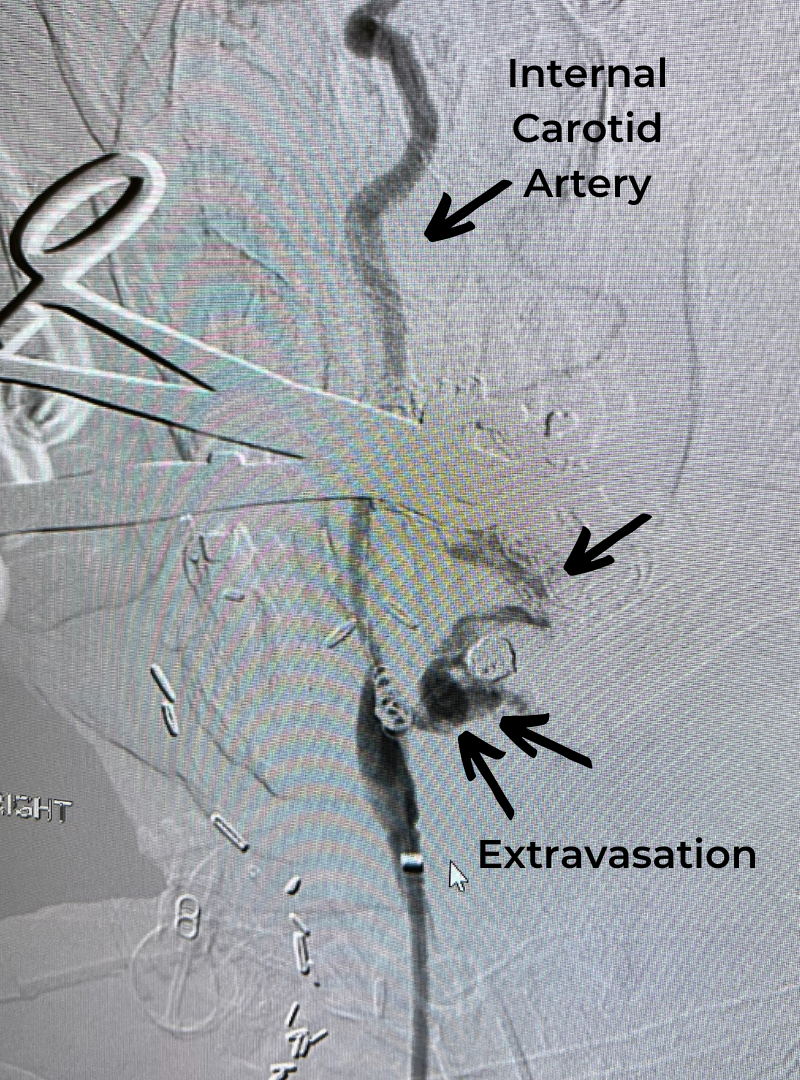

Figure 1. T2 MRI sagittal and axial showing C3/C4 disc herniation with compression of the spinal cord; spinal cord edema at the C3/C4 level.

This patient was suffering from compression of the cervical spinal cord. The fall caused an acute herniation of the cervical disc, which caused pressure on the spinal cord.

This particular spinal cord injury is called Central Cord Syndrome. This type of spinal cord injury typically affects the hands more than the legs and requires urgent surgical attention.